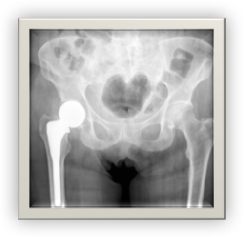

• The following Smith & Nephew hip implants have been recalled:

• REDAPT Hip SystemsRecalled in 2016: In late 2016, Smith & Nephew issued a recall on its Modular REDAPT Hip Systems “due to a higher than anticipated complaint and adverse event trend” with the design of the device.

• Birmingham Hip Resurfacing SystemRecalled in 2015: In June of 2015, Smith & Nephew issued a recall of the smaller sized components of its Birmingham Hip Resurfacing System. The company discovered that patients with this system had revision rates that exceeded certain benchmarks. Based on this, Smith & Nephew considered these patients to be at a higher risk of revision surgery and removed these products from the market.

• R3 Acetabular SystemRecalled in 2012: The R3 Acetabular System was recalled worldwide in 2012 because of reports of device failure, pain, metal sensitivity and other complications.

• Emperion Modular Hip SystemNot yet recalled: While it has not been recalled, the FDA also received numerous adverse event reports concerning Smith & Nephew’s Emperion Modular Hip System. These reports include patients suffering fractures of their hip implants and needing painful revision surgeries.

• SERIOUS COMPLICATIONS from Metal-on-Metal hip implants can include:

• Implant Failure

• Need for Revision Surgery

• Elevated levels of cobalt and/or chromium in the blood

• Diagnosis of metallosis

• Loosening of the device

• It has been reported that metal-on-metal hip replacements have the highest failure rate and fail at a rate of over 10%; meaning that many patients will need to endure costly and painful revision surgery.